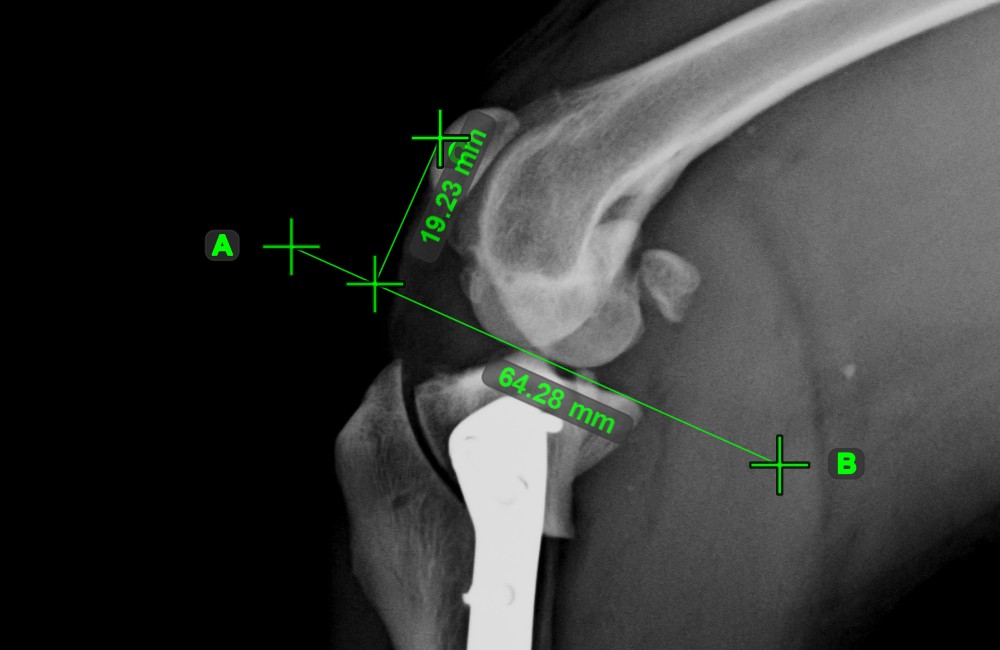

Line Measurement

../_images/image61.jpg

Create a line measurement to calculate the distance between two points with high precision.

Select the Line Measurement tool and assign it to one of the available mouse buttons. Place the start and end points on the scene or select them from already existing points on the image. The distance between the two points will be automatically calculated by using the default calibration data, or the recalibrated data by the length calibration measurement.

Modify the start and end point by using the Select/Move Item tool. The distance between the two points will be automatically recalculated.

../_images/image164.jpg